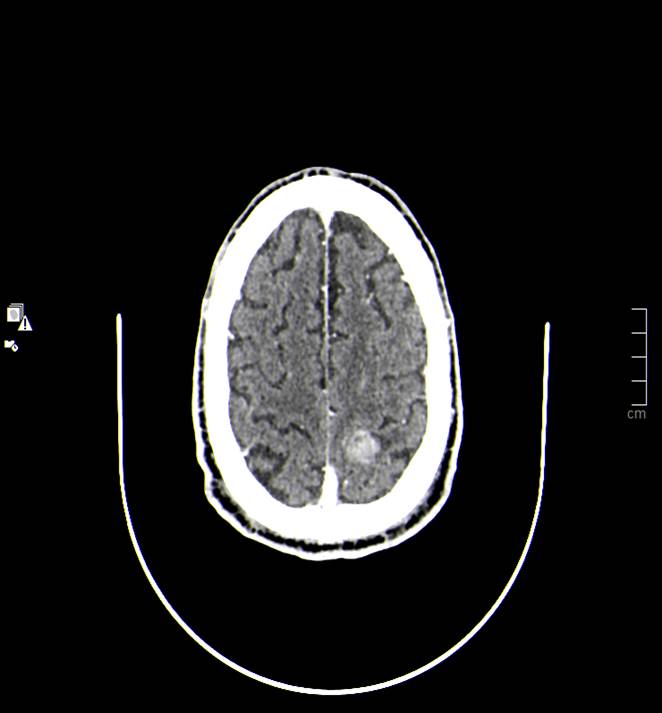

Caso 36

Beatriz Navarro Valverde